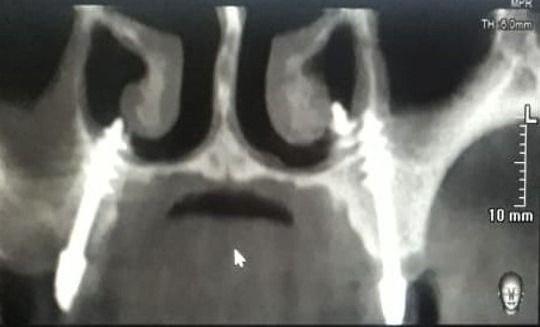

Bi-cortical Engagement

Master the art of bicortical engagement for unmatched implant stability. Learn advanced corticobasal techniques, including nerve bypass, ensuring immediate loading and longterm success.

Live training in bicortical planning, nerve bypass, sinus avoidance

Nerve bypass is an important technique to rehabilitate the posterior mandible without risking inferior alveolar nerve injury. It allows placement of implants in severely resorbed jaws while avoiding neurosensory complications.